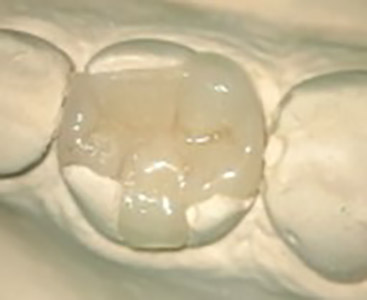

Gentle and painless treatment of dental caries and dental lesions using the most modern techniques and materials from renowned companies with emphasis on aesthetics and functional tooth restoration.

We produce photocomposite, ceramic (inlay, onlay) and amalgam fillings of the latest generations.